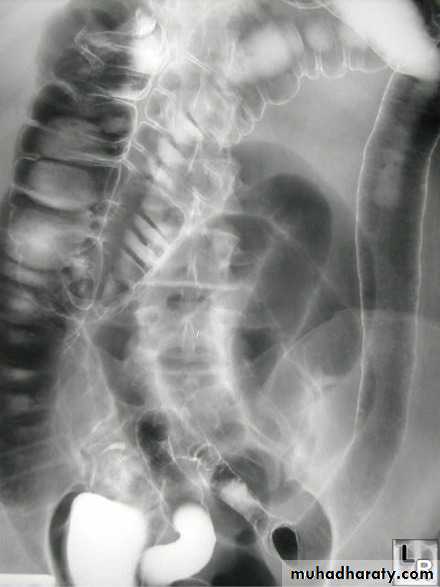

Radiographic features

The characteristic of Crohn's disease is the presence of skip lesions. The frequency with which various parts of the gastrointestinal tract are affected varies widely :small bowel : 70 - 80 % + regional ileitis

X-Ray Manifestations

• Squaring of the folds-early manifestation from obstructive lymphedema• Apthous ulcers-small nodular filling defects (mound of edema) with central ulceration

• Skip lesions-discontinuous involvement of the bowel with intervening normal areas

• Cobblestoning-irregular, blanket-like appearance to bowel wall caused by criss-crossing longitudinal and transverse ulcers separated by areas of edema

• Pseudopolyps-islands of hyperplastic mucosa between denuded areas of mucosa

• Filiform post-inflammatory polyps

• Pseudodiverticula-from bulging area of normal wall opposite side of scarring from disease, usually on anti-mesenteric side

• String-sign-marked narrowing of terminal ileum (usually) from a combination of edema, spasm and (sometimes, but not always) fibrosis; frequently associated with proximal dilatation